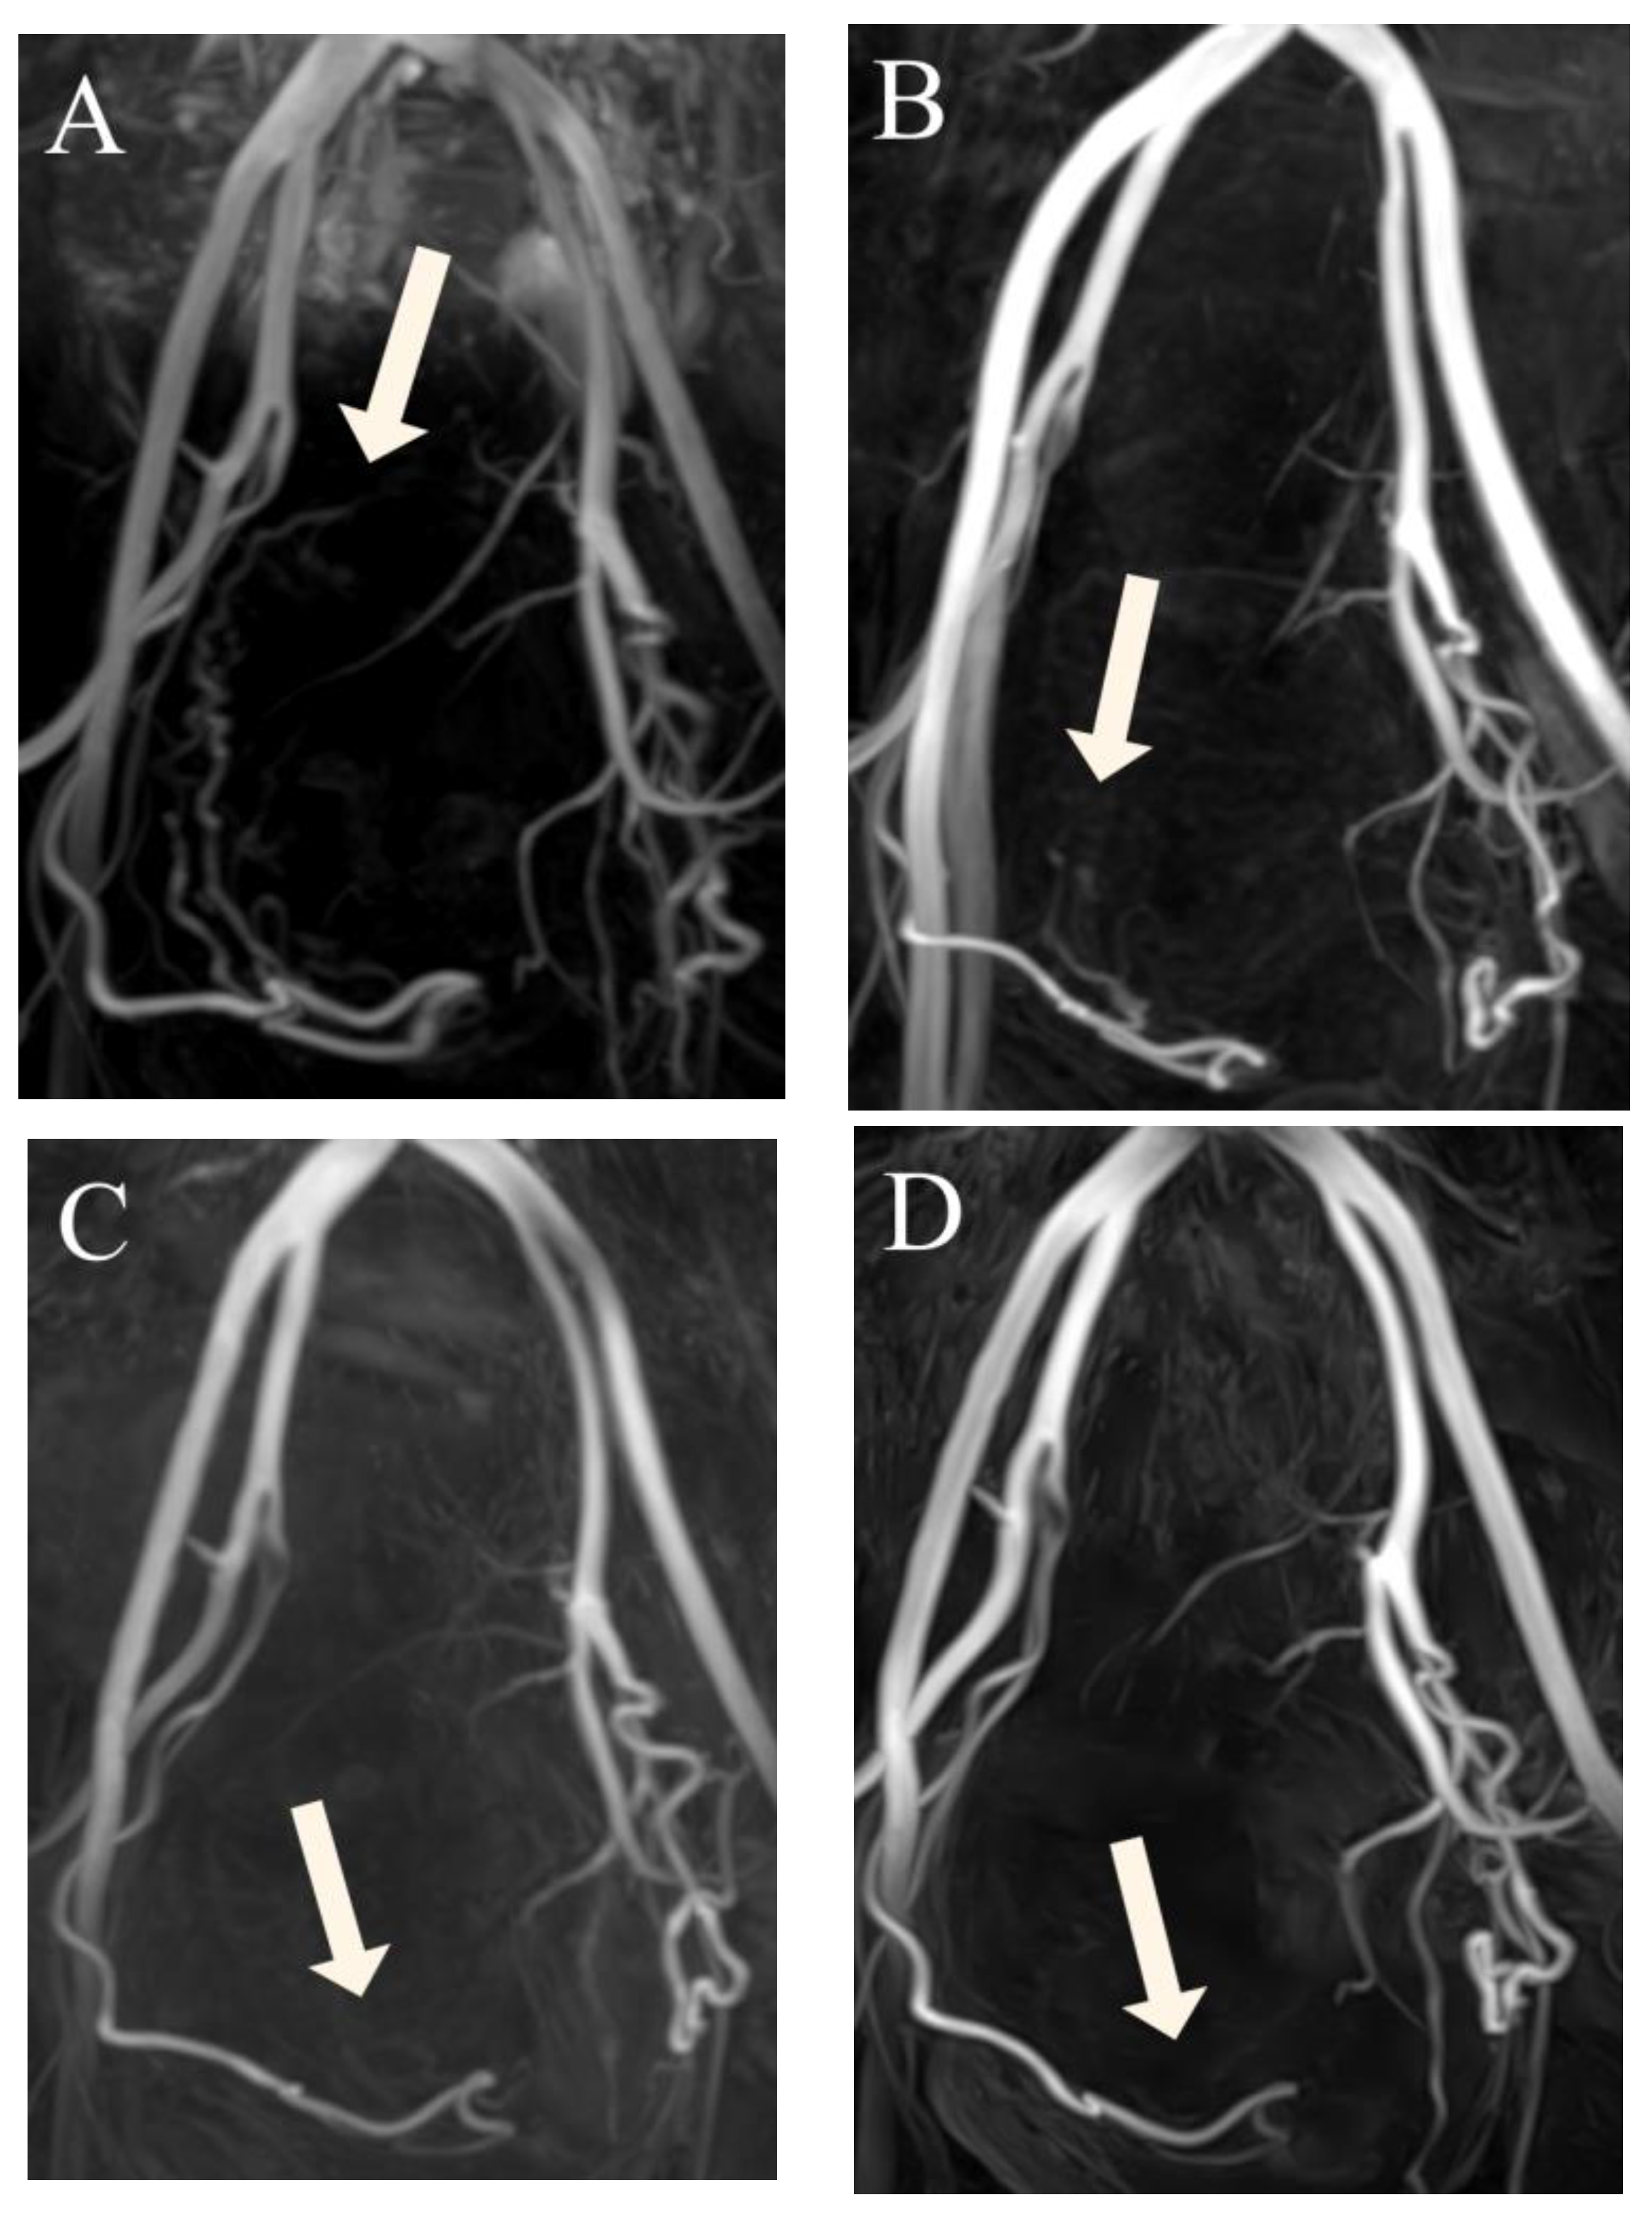

Figure 4.

(A–D) Three-dimensional non-contrast-enhanced magnetic resonance angiography image from a 48-year-old woman, suggesting that luminal recanalization of the uterine arteries did not occur after uterine artery embolization. (A) Before uterine artery embolization: visualization of the right UA (arrow) forming the peritumoral plexus (score 4). (B) Three months after uterine artery embolization: visualization of the right uterine artery (arrow) until the ascending segment (score 3). (C) Six months after uterine artery embolization: visualization of right uterine artery (arrow) until the transverse segment (score 2). (D) Twelve months after uterine artery embolization: visualization of the right uterine artery (arrow) until the transverse segment (score 2).